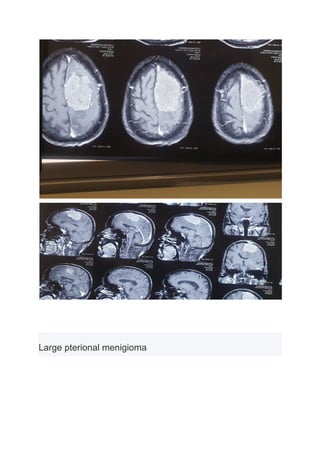

Large pterional menigioma